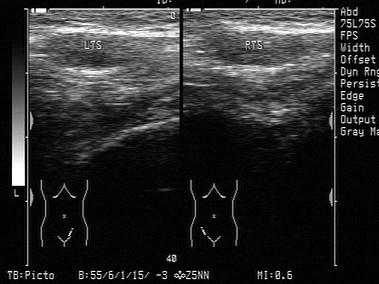

问题 男,11岁,右侧阴囊空虚,左侧睾丸可触及,右侧腹股沟区可探及低回声肿块,如图所示,考虑为?(?)

选项 A.隐睾 B.淋巴结 C.腹股沟疝 D.腹股沟肿瘤 E.以上都不是

答案 A